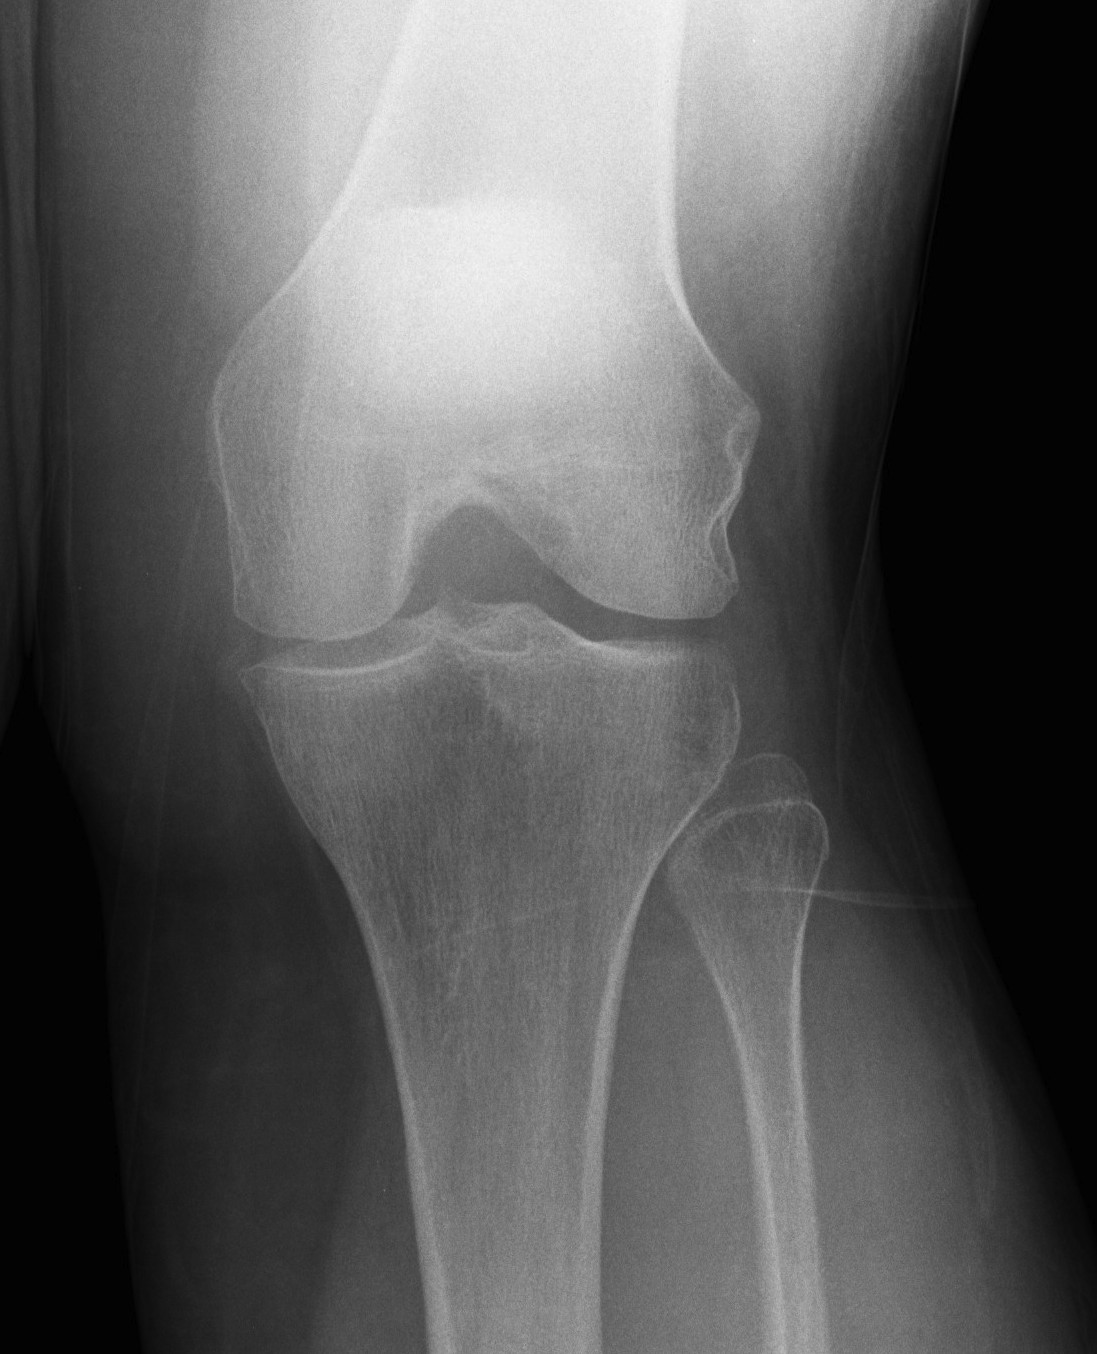

Rosenberg view / tunnel view

- 45o flexion weight bearing view

Rationale

- most early cartilage loss is in 30-60o flexion range

- can be missed with view in extension